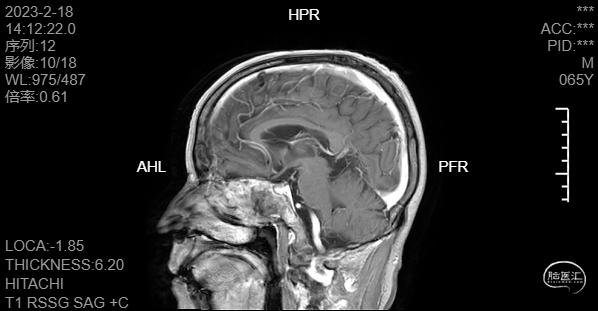

头颅磁共振T2冠矢状位平扫提示积液主要位于蝶窦腔内,筛窦及上颌窦相对干净,且未见明显占位征像。

术后MR增强复查